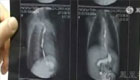

拍客:宁夏男童误食强碱 食道腐蚀扭曲